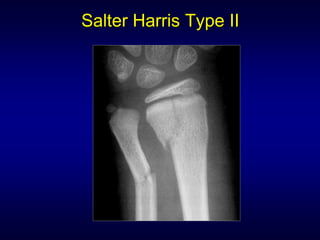

Salter Harris classification

I     S   = SLIPPED/separated

II    A   = ABOVE

III   L   = LOWER

IV    T   = THROUGH/together

V     R   = RAMMED/ruined

Salter Harris Type II